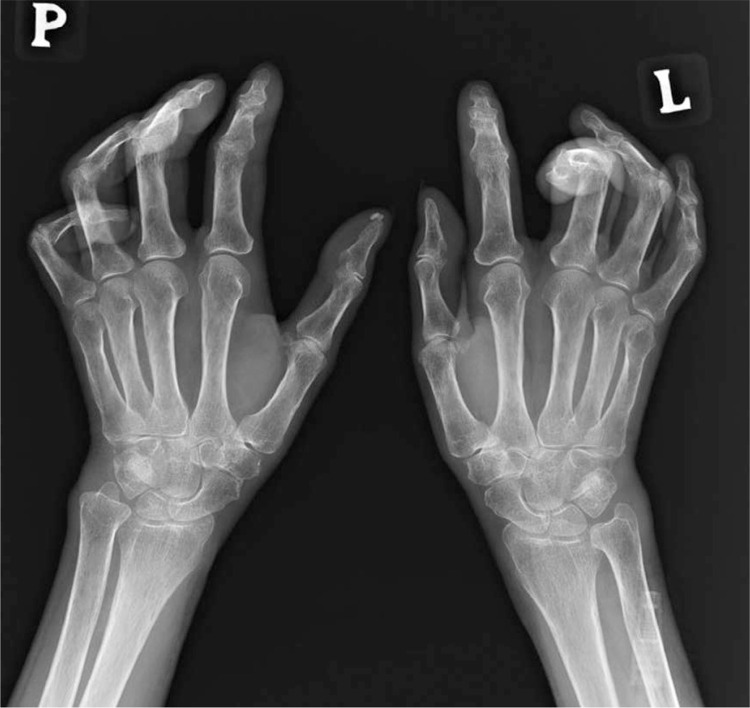

系统性硬化症(SSc)是一种多器官、全身性结缔组织疾病,会影响肺、心脏、胃肠道、肾脏、皮肤和肌肉骨骼系统。40%-90%的 SSc 患者会出现肌肉骨骼受累。患病期间,骨骼、关节、腱鞘、肌腱和肌肉等肌肉骨骼系统的任何结构都可能受到影响。最常见的症状包括关节疼痛、关节炎、导致肌腱断裂的肌腱炎、关节骨溶解、钙化、肌痛和肌炎。骨关节并发症和手部软组织的变化会导致手指挛缩,从而导致患者生活质量下降和残疾。总之,更详细地了解导致肌肉骨骼系统渐进性变化的病因,可能有助于引入新的治疗方案,从而改善 SSc 患者的生活质量并减少残疾。

Systemic sclerosis (SSc) is a multi-organ, systemic connective tissue disease, which affects the lungs, heart, gastrointestinal tract, kidneys, skin, and musculoskeletal system. Musculoskeletal involvement is observed in 40-90% of patients with SSc. During the disease, any structure of the musculoskeletal system, such as bones, joints, tendon sheaths, tendons, and muscles, may be affected. The most common symptoms include joint pain, arthritis, tendinitis leading to tendon rupture, acro-osteolysis, calcinosis, myalgia, and myositis. Osteo-articular complications and changes in the soft tissues of the hand lead to finger contracture, which causes deterioration of the patients' quality of life and disability. To sum up, a more detailed understanding of the aetiology leading to progressive changes in the musculoskeletal system may contribute to the introduction of new therapeutic options, and thus improve the quality of life and reduce disability in patients with SSc.